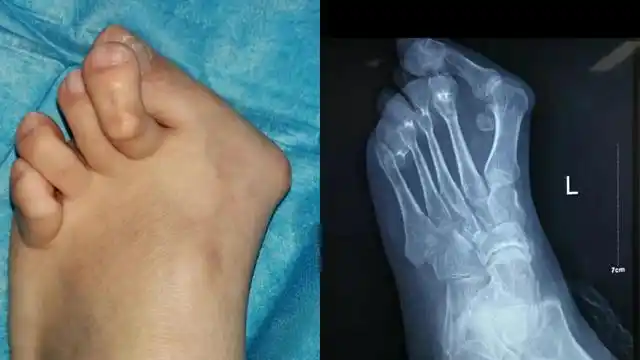

大脚骨整形专家 的想法: 虽然说#痛风# 也会导致第一跖趾关节凸起

俗称"大脚骨",现行右足矫形,软组织,籽骨松解复位 chevron截骨 关节囊

大脚骨,踇外翻畸形 - 好大夫在线